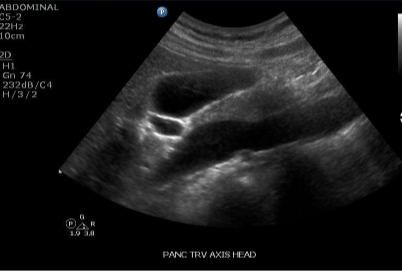

Trv Pancreas Head- anterior to IVC with CBD

(more sag hold from hamburger to right little)